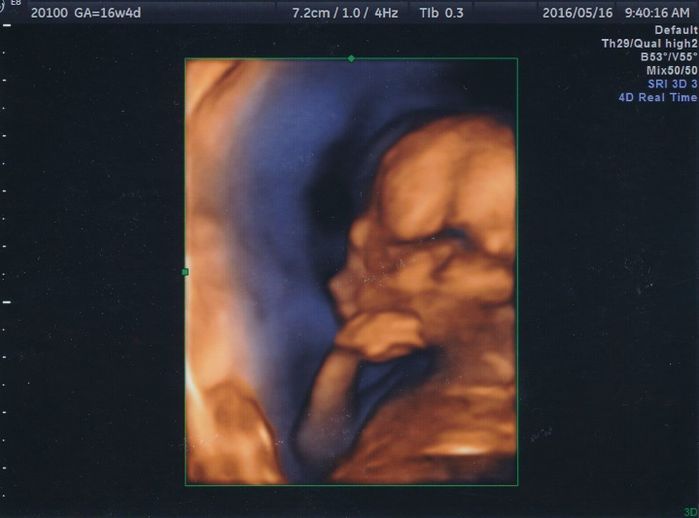

妊娠16週目のエコー写真

赤ちゃんの顔が正面からはっきり写っています。目鼻立ちも分かるので、赤ちゃんの顔を想像していたように思います。あごの近くにある2つの白丸は小さな両手です。

こちらは4Dです。赤ちゃんが指しゃぶりをしているところが撮れました。実際には口がパクパクと動いていたように記憶しています。

こちらも4D写真で、先ほどの指しゃぶりを画面でじっと見ていたら本人に気づかれたのでしょうか。やめてしまいました。流産のリスクが高い妊娠初期を乗り切ったら、次に待っていたのは赤ちゃんに異常がないかどうかの不安でした。